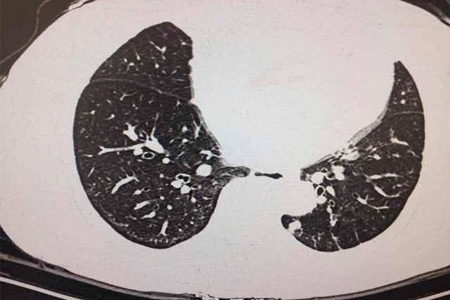

肺癌是一種常見的惡性腫瘤,其發生與多種因素有關,包括遺傳因素。近年來,随着基因檢測技術的發展,人們越來越關注其在預測肺癌患病風險中的作用。

随着基因檢測技術的發展,越來越多的研究表明,基因檢測可以幫助預測個體患肺癌的風險。通過檢測個體的基因變異情況,可以評估其患肺癌的風險,從而采取針對性的預防措施。